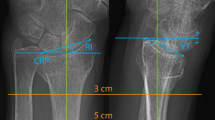

This study evaluates the morphometric characteristics of the volar distal radius, specifically volar curvature, scaphoid and lunate facet inclinations, and ulnar variance, in the Anatolian population. By identifying these population specific morphological variations, the study seeks to support improved anatomical compatibility of volar implants and enhance surgical planning for distal radius fracture fixation. Morphometric measurements were analyzed retrospectively on three-dimensional computed tomography images of 103 intact distal radii. Standardized sagittal sections were created through the midpoints of the scaphoid and lunate fossae, and volar curvature was quantified as the angle between the radial shaft axis and the volar cortex at 1 cm and 2 cm proximal to the distal radius volar rim on each section. Volar inclination angles were measured at 1 cm and 2 cm. Additionally, volar width (G), scaphoid facet inclination (SFI), lunate facet inclination (LFI), interfacet angle (IFA), and ulnar variance were evaluated. Volar curvature measured 1 cm and 2 cm proximal to the scaphoid and lunate fossae was significantly greater in males than females (p < .05). The mean transverse volar width was 26.5 mm, with no significant differences according to gender, age, or laterality (p > .05). The mean ulnar variance was − 2.0 ± 2.2 mm, while the mean LFI, SFI, and IFA were − 0.1° ± 8.4°, 26.1° ± 6.9°, and 24.2° ± 10.4°, respectively. This study demonstrates notable anatomical variations in the volar distal radius within the Anatolian population, particularly in volar curvature, scaphoid and lunate facet inclinations, and ulnar variance. These population specific morphometric differences underscore the importance of integrating multiple volar parameters into preoperative planning, as they may directly influence implant selection and improve the accuracy of distal radius fracture fixation.